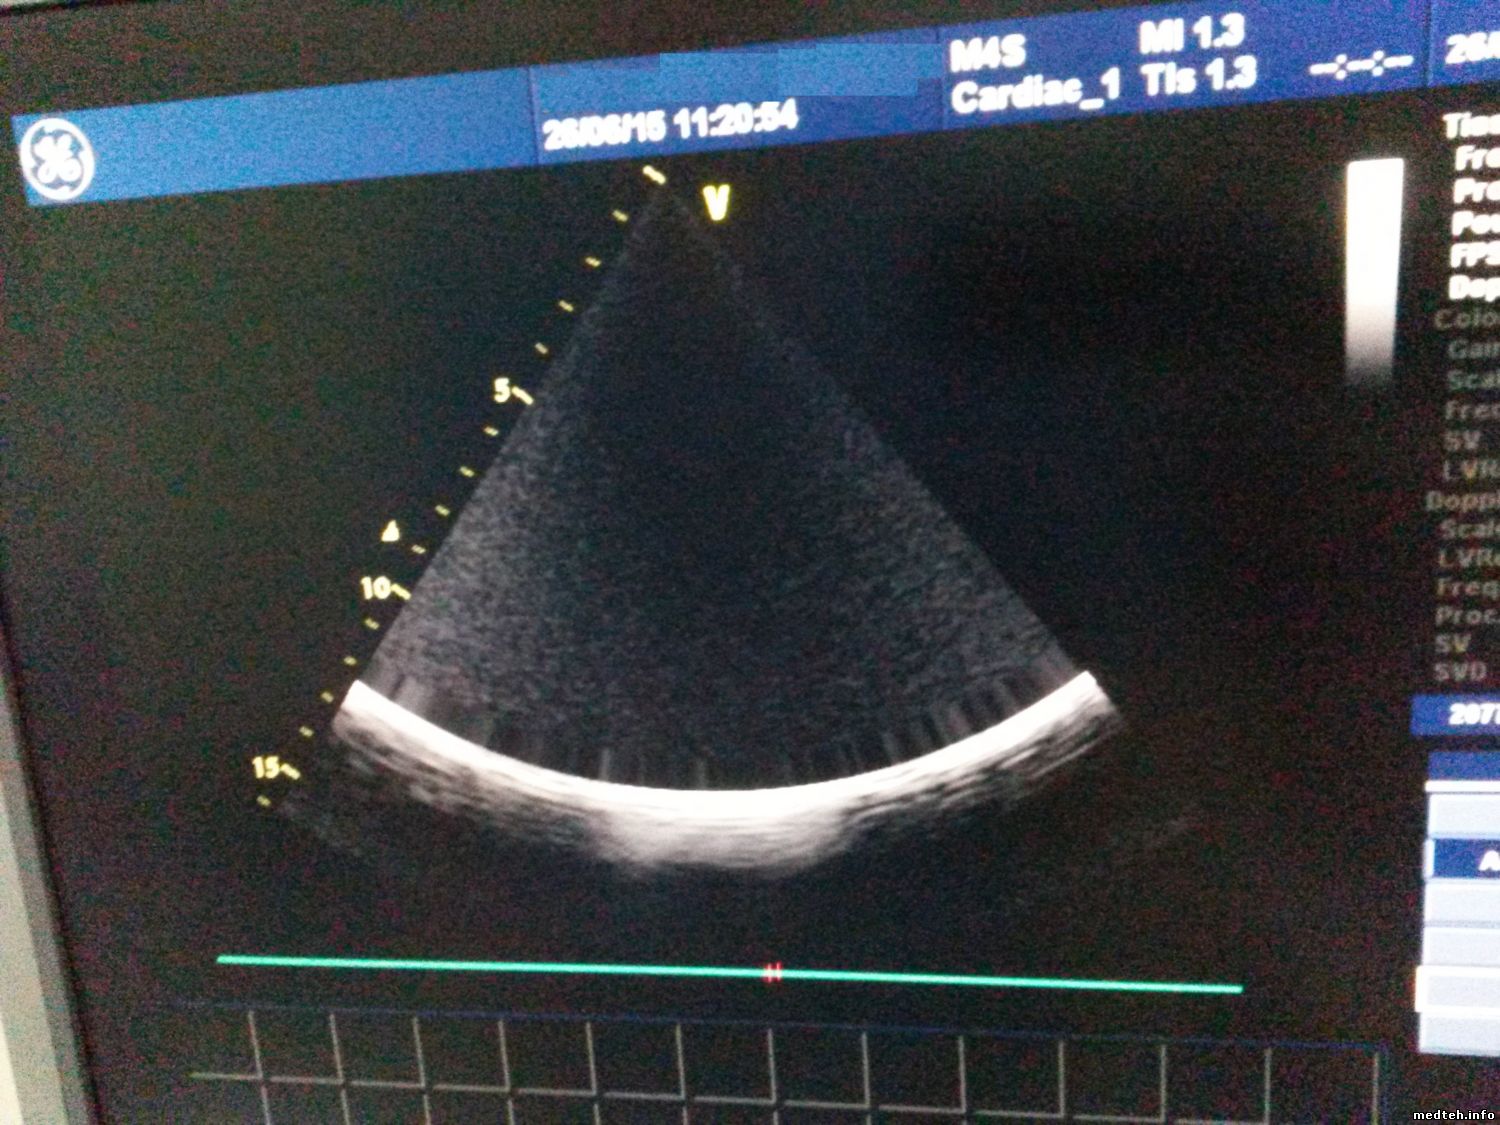

Доброго времени суток! Аппарат Vivid 7 2008 года начал глючить на 2D режиме, смещается область из самого верха в самый низ, одновременно появились глюки на CW режиме, появились импульсы (https://yadi.sk/i/l5kk5LnOhXpdv), причем датчика даже не надо касаться, импульсы есть на разных датчиках и в разных портах. В логах температуры есть довольно высокие значения на TD2 (от 60 до 98 гр.), где находится этот датчик? Аппарат вычищен от пыли, все вентиляторы работают, тесты проходят, кроме тех для, которых нужны адаптеры (адаптеров нет), в чем может быть проблема?

6520931.jpg (202.5 Kb)